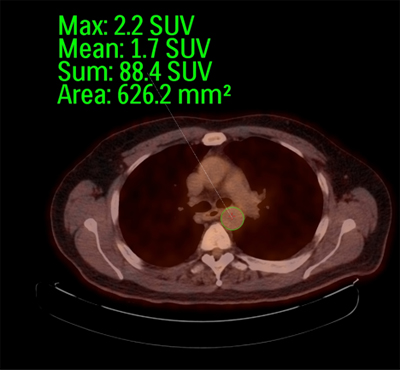

Quantification Of Atherosclerotic Plaque Activity And Vascular Inflammation Using 18 F Fluorodeoxyglucose Positron Emission Tomography Computed Tomography Fdg Pet Ct Protocol Translated To French